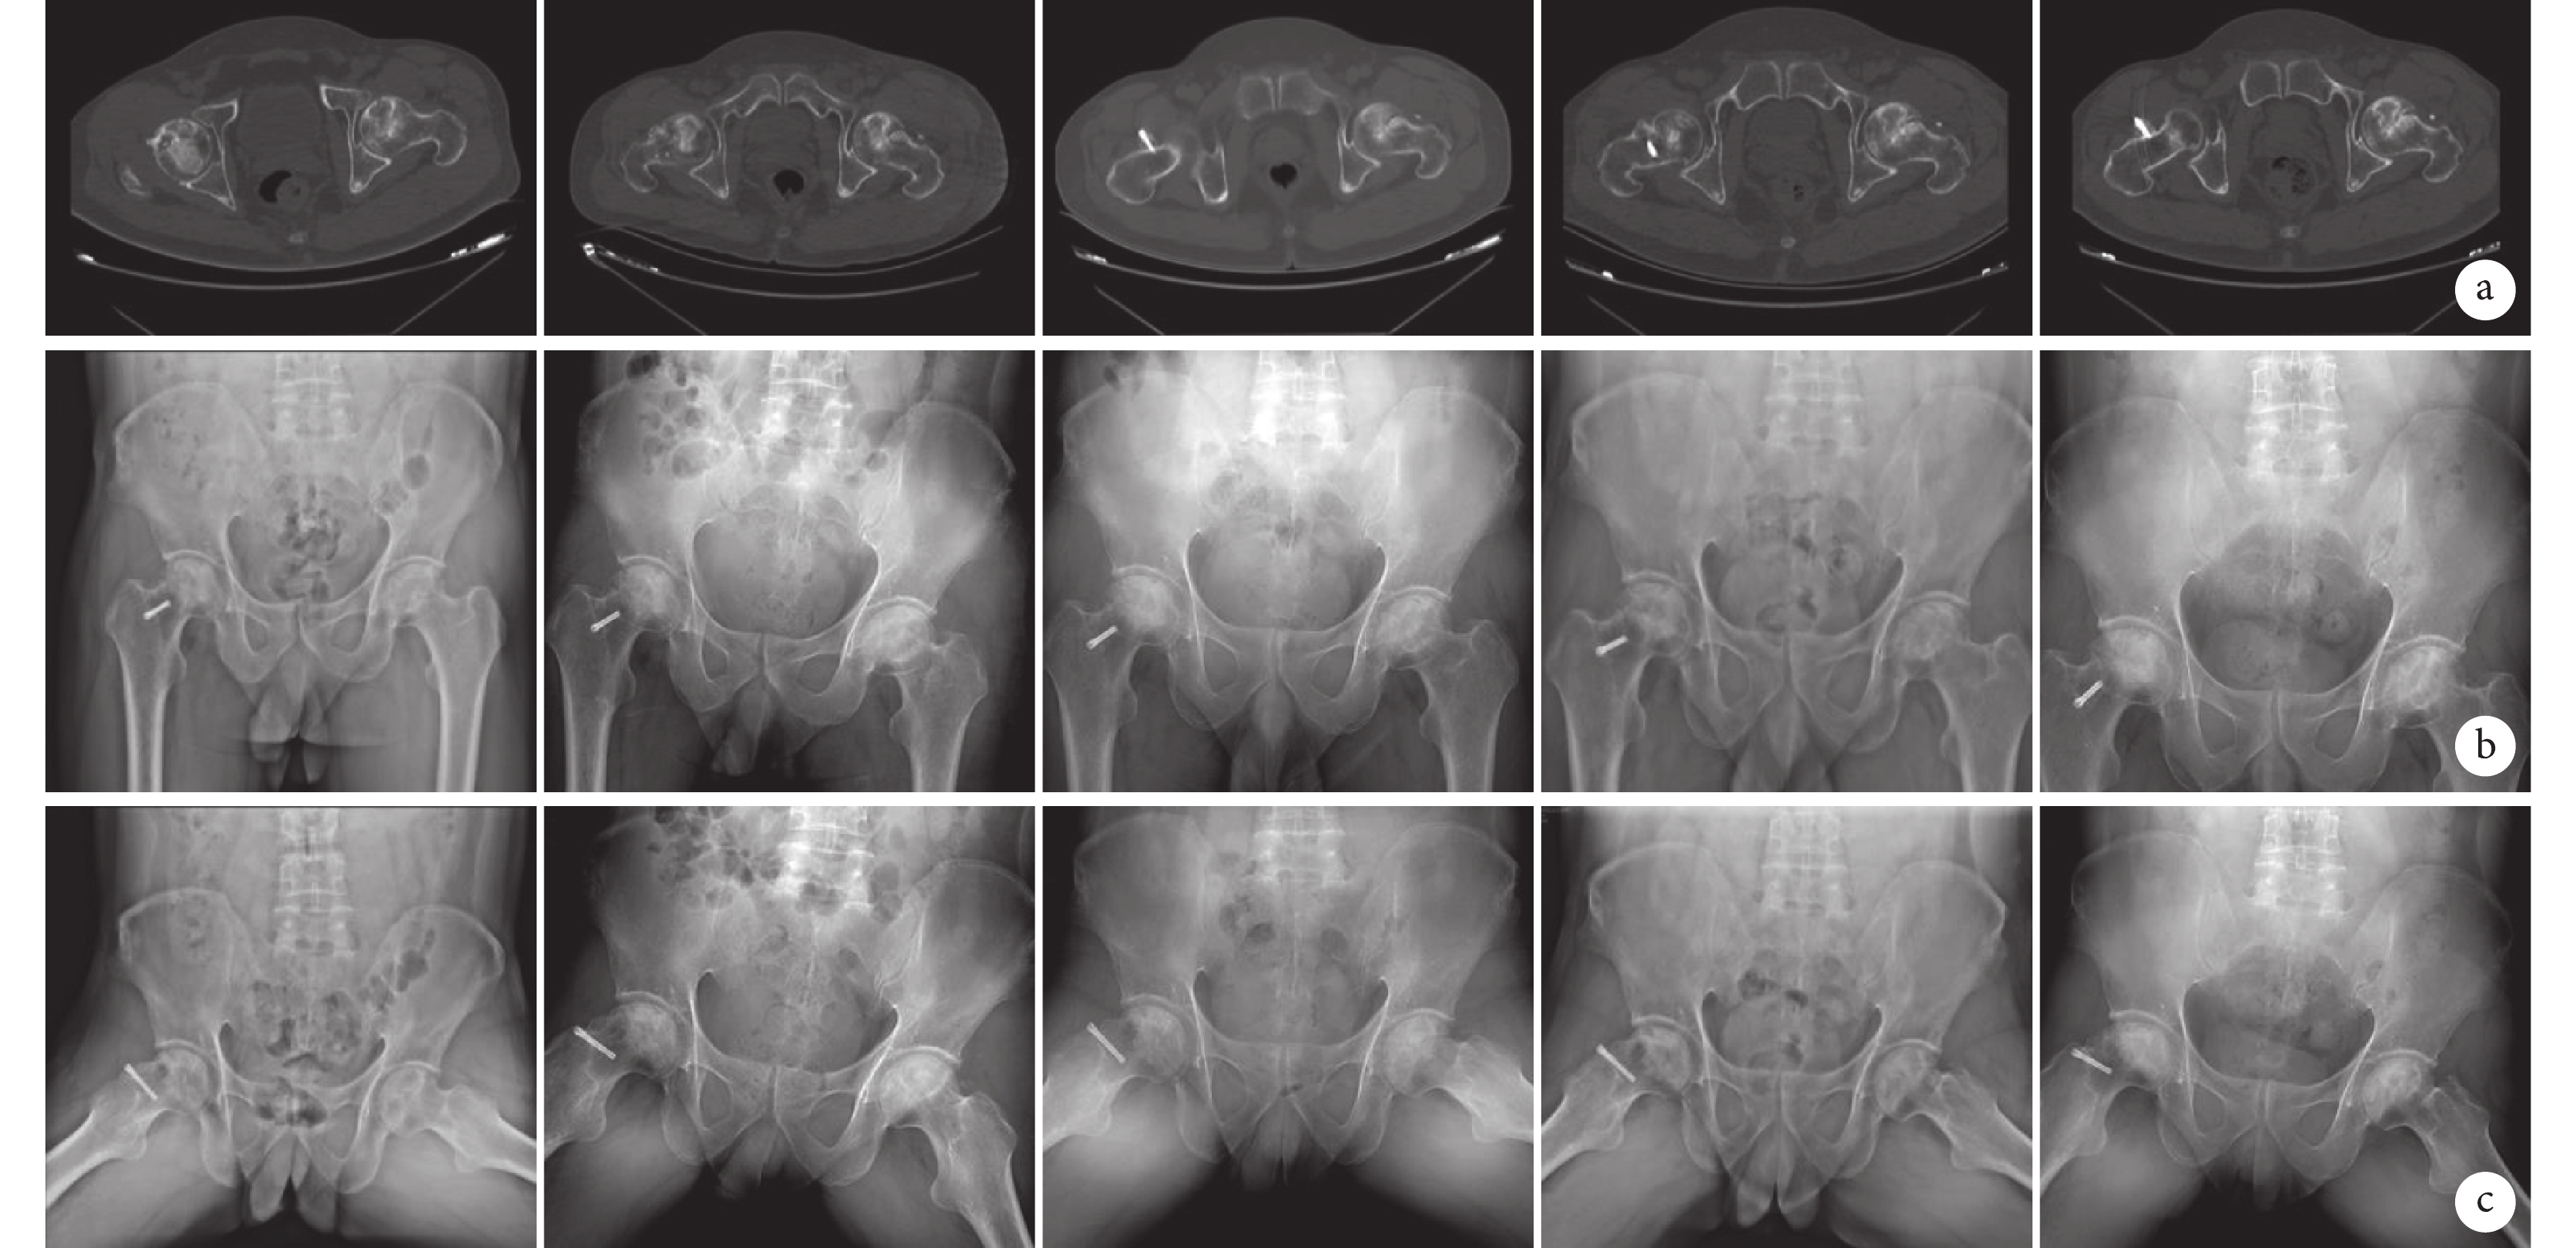

圖5

試驗組患者,男,31歲,左側ONFH(ARCO Ⅱ期)

從左至右分別為術前及術后2周、3個月、6個月、1年 a. CT;b. 骨盆正位X線片;c. 骨盆蛙式位X線片

Figure5. A 31-year-old male patient with the left ONFH (ARCO stage Ⅱ) in the trial groupFrom left to right for the images before operation and at 2 weeks, 3 months, 6 months, and 1 year after operation, respectively a. CT; b. Pelvic X-ray films of anteroposterior position; c. Pelvic X-ray films of frog position

髖關節CT和骨盆正位及蛙式位X線片復查示,兩組髂骨瓣均長入股骨頭內,術后1年時與股骨頭頸交界區開窗處達骨性融合,隨訪期間未見髂骨瓣松動、脫落及移位(圖5、6)。試驗組:術后新型可降解鎂骨內固定螺釘周圍有一過性低密度區,為螺釘溶解吸收征象,期間未見螺釘斷裂及脫落現象;隨時間延長,螺釘直徑逐漸減小,由最初的4.0 mm減小為術后3個月(3.68±0.02)mm、6個月(3.46±0.06) mm、1年(2.98±0.10) mm,差異均有統計學意義(P<0.05)。